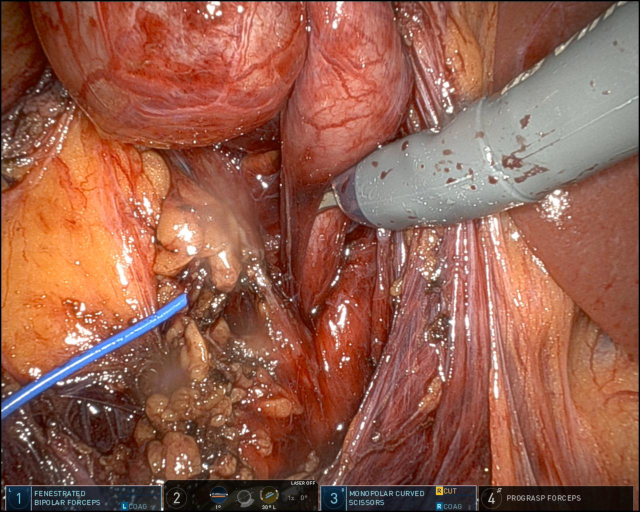

In diesem Fallbericht beschreiben wir einen 17-jährigen Patienten, der mit rez. ausgeprägten Koliken in unserer Abteilung vorstellig wurde. Initial erfolgte bei Hydronephrose °III und pos. Steinanamnese des Vaters eine CT-Abdomen nativ, welche bereits den V.a. einen retrocavalen Harnleiter rechts ergab. Eine Szintigraphie bestätigte eine urodynamisch relevante Obstruktion bei ausgeglichener Nierenfunktions. Bei Symptomatik erfolgte eine retrograde Ureteropyelographie mit JJ-Einlage. Im weiteren Verlauf wurde noch eine MRT-Angiographie durchgeführt, welche den Befund eindeutig bestätigte. Daraufhin erfolgte am 10.11.2025 die daVinci-assistierte Ureterureterostomie rechts in Linksseitenlage. Hierfür wurden 4 Arbeitstrokare und ein Kameratrokar verwendet. Die Gesamtoperationszeit lag bei 181 min, die reine Konsolenzeit bei ca. 100 min. Intraoperativ erfolgte ein JJ-Wechsel. Die Anastomose erfolgte mit einer 4.0 Quill-Naht in fortlaufender Technik. Der Blutverlust lag bei ca. 20 ml. Postoperativ waren die Schmerzen mit Novalgin gut beherrschbar. Die Entlassung erfolgte am 5. postoperativen Tag nach DK-Entfernung.

Die robotisch assistierte Operation eines retrocavalen Harnleiters stellt unserer Meinung heutzutage den Goldstandard dar. Die Operation kann sicher und mit sehr niedrigem Risiko durchgeführt werden. In der Literatur liegen die mittleren OP-Zeiten für die Laparoskopie über denen für die robotische Rekonstruktion, ebenso ist der Blutverlust für die robotische Technik niedriger. Eine offene Operation sollte heutzutage bei diesem Krankheitsbild möglichst vermieden werden.

Abbildung 1 [Abb. 1], Abbildung 2 [Abb. 2], Abbildung 3 [Abb. 3], Abbildung 4 [Abb. 4], Abbildung 5 [Abb. 5], Abbildung 6 [Abb. 6], Abbildung 7 [Abb. 7], Abbildung 8 [Abb. 8], Abbildung 9 [Abb. 9], Abbildung 10 [Abb. 10]